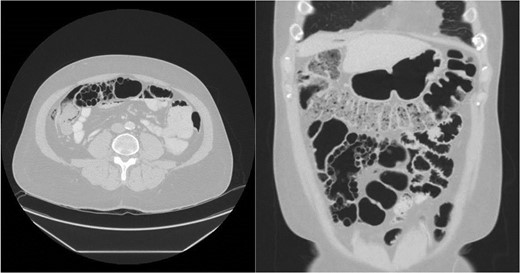

CT abdomen pelvis with IV contrast demonstrating cystic pneumatosis coli.

Multiple submucosal air pockets (cysts) ranging in size from 0.3 to 1.5 cm.